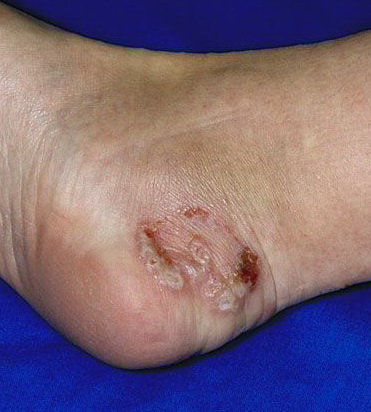

Acute Ulcerative Type.

Rampant bacterial co-infection, most often from Gram negatives in combination with T. mentagrophytes, produces vesiculopustules and large areas of purulent ulceration on the plantar surface. Cellulitis, lymphangiitis, lymphadenopathy, and fever are frequently associated.

The vesiculo-bullous and acute ulcerative types commonly produce a vesicular id reaction, either as a dyshidroticlike distribution on the hands or on the lateral foot or toes.